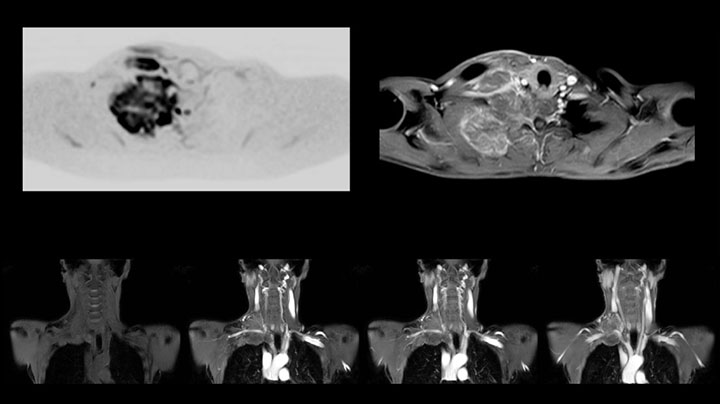

MRI of Pancoast tumor

Although the area between the neck and the top of the lung is one of the most difficult areas for MRI, Prodiva 1.5T images show good quality in this 56-year-old male with Pancoast tumor on the right. mDIXON TFE images shows excellent fat suppression in the neck area and the DWI shows almost no distortion.

Prodiva MRI pancoast tumor DWI, Seirei Mikatahara

Prodiva MRI pancoast tumor mDixon, Seirei Mikatahara

Prodiva MRI pancoast tumor dynamic, Seirei Mikatahara

This patient is a 43-year-old female with a left supraclavicular nerve sheath tumor. The lesion is well visualized on the STIR VISTA images and on the MR neurography using DWIBS. The exam was performed on Prodiva 1.5T.

Whole body diffusion

MR neurography using DWIBS inverted, full MIP

Acq voxel size 1.2 x 1.3 x 2.4 mm, Recon voxel size 0.7 x 0.7 x 1.2 mm, dS SENSE factor 2, scan time 5:46 min.